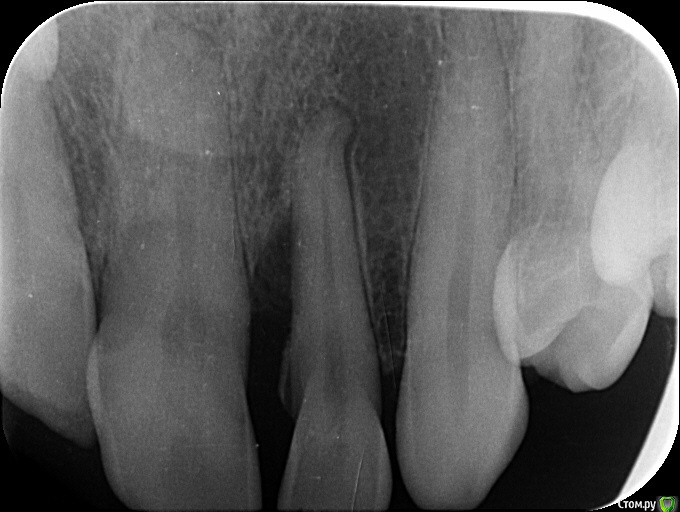

analgin Опубликовано 28 июня, 2018 Поделиться Опубликовано 28 июня, 2018 (изменено) Добрый день! Пациентка, 43 года, жалобы на гиперемию, отек десны в области 2.1 и 2.2 зубов. Статика зубов не нарушена. Удалять зуб не хочет. Подскажите план лечения. Изменено 28 июня, 2018 пользователем analgin Ссылка на комментарий

Евгений Ходыкин Опубликовано 29 июня, 2018 Поделиться Опубликовано 29 июня, 2018 Скорее всего потребуется эндо. А далее наблюдение за восстановлением кости... Ссылка на комментарий